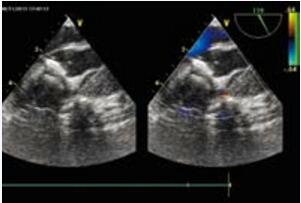

笔者第一次遇到这种情况是在进行肌部室间隔缺损封堵时,传统的胸骨切口并不是封堵某些缺损的最佳入路。当然,可能通过旋转拖拉可以把心脏通过切口暴露出来,但是切口越小孩子越大越难操作。而且植入封堵器的直行方向会消失,从而导致封堵器超声图像形态变形。经食管超声心动图图像在心尖部卷曲的情况下也会变得复杂。对于这些病人,笔者设计了一种非常简单而且比标准方法更美观的手术,特别适用于极度靠近心脏前部几乎没有间隔边缘的心尖部缺损患者。患者向右旋转20~30度(图10-44),心脏上缘的探查借助经胸超声心动图进行,由第4 肋间入路(图10-45),此方法可以无需任何牵引精确到达心脏上部和室间沟,清晰的暴露穿刺位置。而且可以按照标准方法直接关闭任何心尖部缺损(图10-46,图10-47)。笔者提供的病例中有一个10月龄、10kg的患儿。选用 SQFDQ 9mm 封堵器封闭7mm的心尖部室间隔缺损。